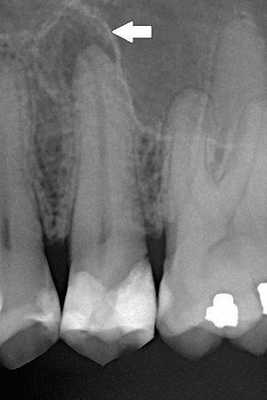

Для диагностики одонтомы, в первую очередь, используются данные клинического осмотра пациента. Для уточнения диагноза обязательно проводится рентгенологическое исследование (ортопантомограмма, КТ челюсти), на котором выявляется ограниченная гомогенная тень. Также используется гистологическое исследование для исключения озлокачествления опухоли. Дифференциальную диагностику проводят с другими опухолями характерными для данной области челюстно-лицевой системы (например, амелобластомой), а также с хроническим остеомиелитом.

Обычно одонтомы находят на плановых профилактических приёмах у стоматолога или в ходе рентгенологических исследований при диагностике других болезней. Растущую одонтому можно обнаружить с помощью обычной рентгенографии, но её тяжело опознать без отложений кальция, т. е. на начальной стадии развития опухоли.

Инструментальная диагностика

В случае сложной одонтомы на рентгенографическом изображении сравнительно хорошо видно организованные деформированные зубы или зубоподобные структуры, похожие на рентгенопрозрачные кисты. Сама одонтома выглядит как образование неправильной овальной формы. Обычно она окружена чётко очерченной тонкой рентгенопрозрачной зоной.